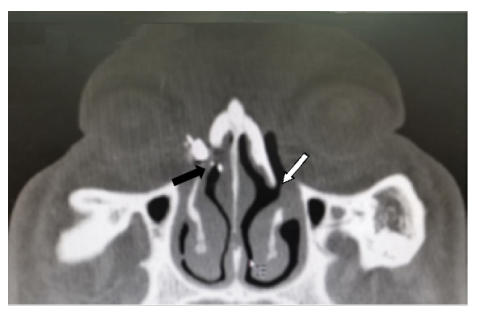

A组43例(44眼),B组39例(39眼),样本数比较差异无统计学意义。两组患者术后随诊慢性泪囊炎均无复发。A组治愈42眼(95.45%),好转2眼(4.54%);B组治愈38眼(97.43%),好转1眼(2.56%)(图5,6),两组比较差异无统计学意义(P>0.05)。B组有12眼(30.77%)使用骨动力系统用于磨削骨孔,A组未使用骨动力系统;A组手术时间为(31.88±1.64) min;B组手术时间为(48.54±4.40) min,两组比较差异有统计学意义(P < 0.01)。

Conventional En-DCR of right eye:Extensive bone removal near medial wall of the lacrimal sac and the ostium was blocked with mucosa thickened. The small sac was filled with high-density contrast.(black arrow)En-LP-DCR of left eye: the ostium located in middle and lower with 1/4 sac with the bone and mucosa near medial wall of the sac preserved mostly.(white arrow).

(A) The perfact ostium and the stent In situ was seen in patient underwent En-LP-DCR combined with new split RT silicone stent intubation three months later (arrow). (B) A successful case with En-LP-DCR combined with new split RT silicone stent intubation 3 months after operation with stent removel.The perfact lower ostium close to the position and size of the physiological inferior orifice of duct (arrow).